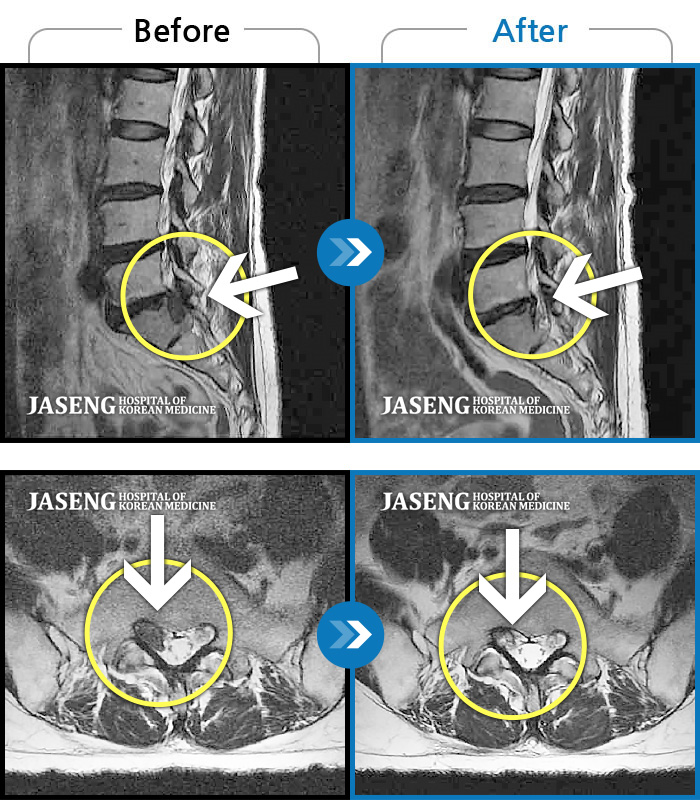

허리디스크

잠실 · 한상욱 원장

허리, 우측 엉치와 다리 후면 및 발끝까지 저림과 통증이 심하고 힘까지 빠진다.

촬영시기

2022.06.15 ~ 2022.11.11

2022.12.02